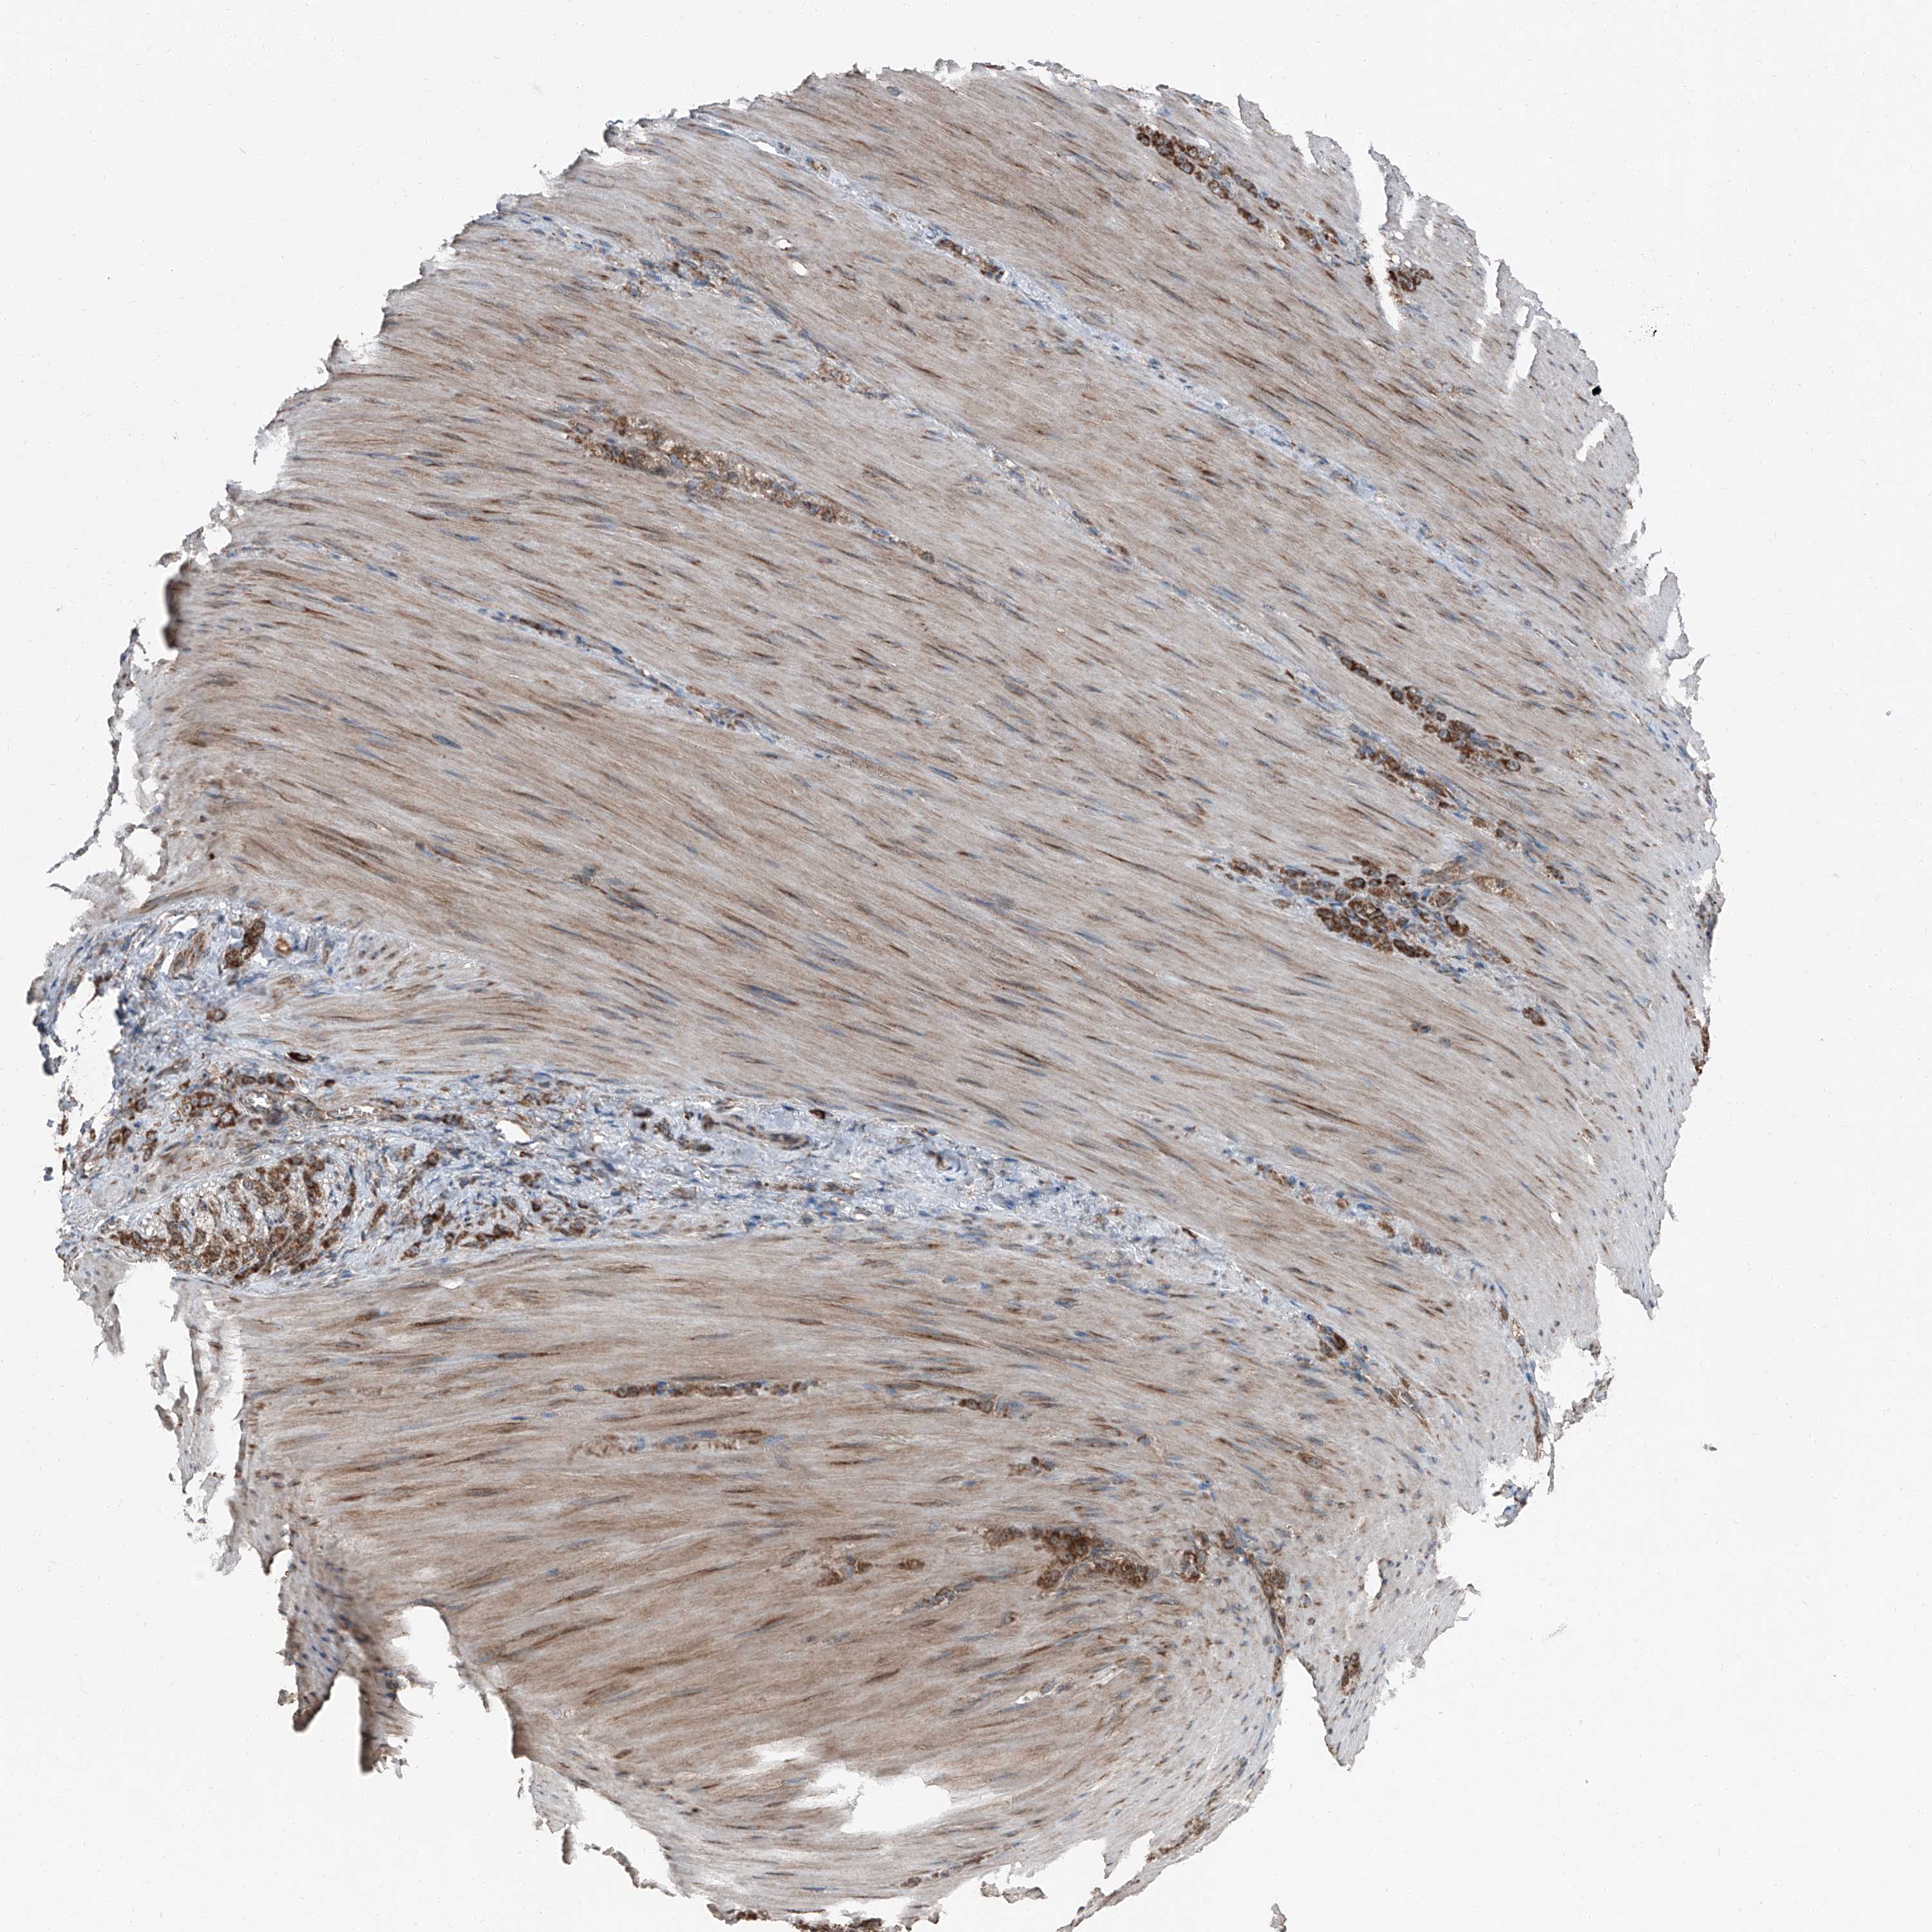

STOMACH CANCER - Protein expressioni

A mouse-over function shows sample information and annotation data. Click on an image to view it in a full screen mode. Samples can be filtered based on level of antibody staining by selecting one or several of the following categories: high, medium, low and not detected. The assay and annotation is described here.

Antibody stainingi

Antibody staining in the annotated cell types in the current human tissue is reported as not detected, low, medium, or high, based on conventional immunohistochemistry profiling in selected tissues. This score is based on the combination of the staining intensity and fraction of stained cells.

Each image is clickable and will lead to virtual microscopy that enables deeper exploration of all samples and also displays staining intensity scores, fraction scores and subcellular localization as well as patient and tissue information for each sample.

Antibody HPA028516

Antibody HPA073571

Staining

High

Medium

Low

Not detected

Intensity

Strong

Moderate

Weak

Negative

Quantity

>75%

75%-25%

<25%

None

Location

Nuclear

Cytoplasmic/membranous

Cytoplasmic/membranous,nuclear

Adenocarcinoma, NOS

Adenocarcinoma, High grade